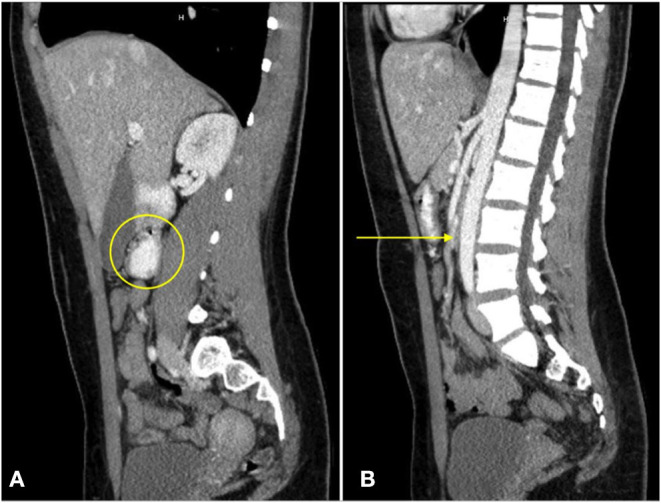

At presentation, the patient reported a rapid weight loss of more than 9 Kg. She denied constipation, diarrhea, or intentional vomiting or weight loss. She was noted to have a normal body mass index (BMI) of 23.46 Kg/m2, despite her weight loss. Physical examination was remarkable for diffuse abdominal tenderness and fullness to palpation, worst in the epigastrium. ß-hCG was again negative and urine toxicology screen was positive for tetrahydrocannabinol (THC). Abdominal x-ray was unremarkable. CT scan with contrast of the abdomen and pelvis revealed moderate gastric and proximal duodenal distention, with tapering of the duodenal lumen at the level of the SMA. The aortomesenteric (AOM) angle was 10 degrees and AOM distance was 6 mm. Taken together, these findings were suggestive of SMAS (Figures 2, 3) (ref. 3). There was no evidence of biliary or pancreatic pathology, adenopathy, or malignancy. A nasogastric tube was inserted for gastric and duodenal decompression and a nasojejunal (NJ) tube was placed to bypass the obstruction and provide nutrition and hydration.

The differential diagnosis for our patient’s acute illness, in addition to SMA syndrome, included: small bowel obstruction, gastric or duodenal dysmotility (e.g., gastroparesis, ileus), collagen vascular disease (e.g., scleroderma), chronic idiopathic pseudo-obstruction, and peptic ulcer disease. The decreased AOM angle of less than 22 to 28 degrees and AOM distance between 2 and 8 mm in association with the patient’s symptoms, however, were diagnostic of SMA syndrome (ref. 8–ref. 10).